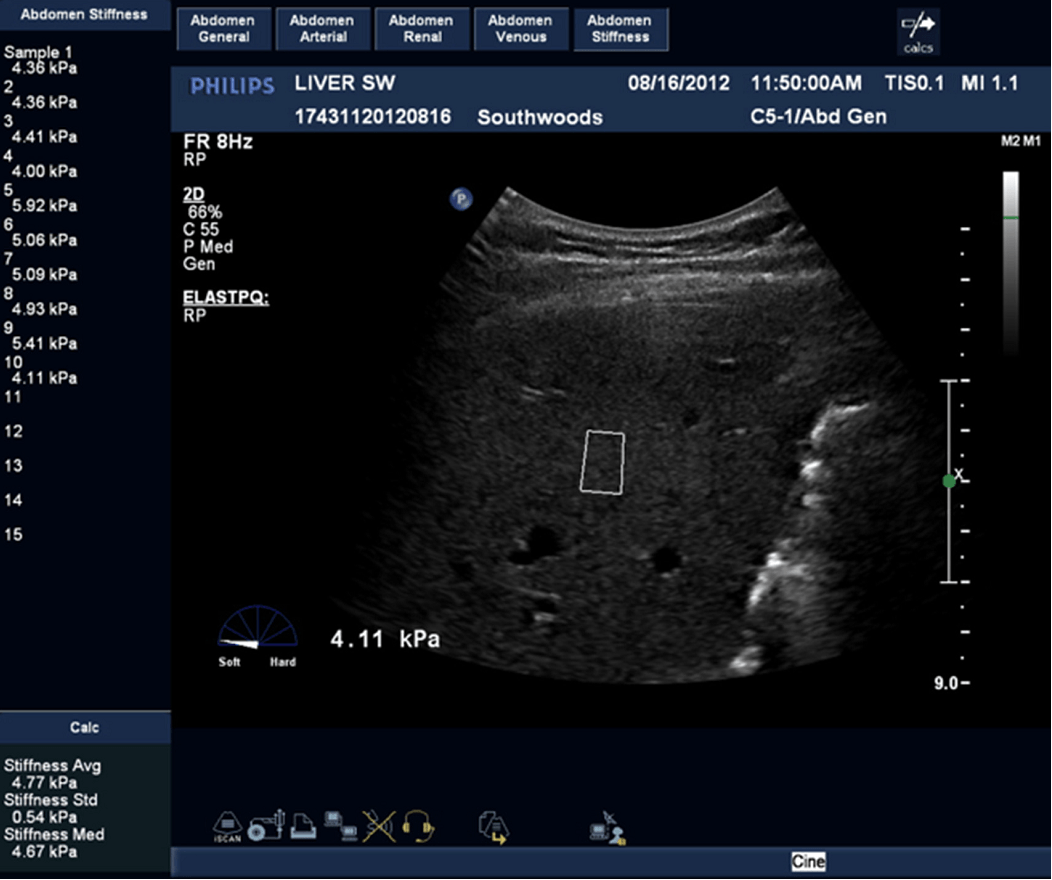

Эластометрия брюшной полости – это современный метод диагностики, который позволяет оценить состояние тканей органов в брюшной полости с помощью ультразвуковых волн. Это исследование помогает выявить различные заболевания на ранних стадиях, таких как цирроз печени, фиброз, воспалительные процессы и другие патологии, что способствует своевременному назначению эффективного лечения.

Эластометрия печени. Что выбрать: фиброскан или УЗИ?

Эластометрия печени. Что? Где? Когда?

Эластометрия печени. Покажет то, что не видно на УЗИ и в анализах.

Эластометрия - как метод мультипараметрического УЗИ. Большое интервью с доктором Пеняевой Э.И.

УЗИ органов брюшной полости и эластография печени на Mindray Resona i9